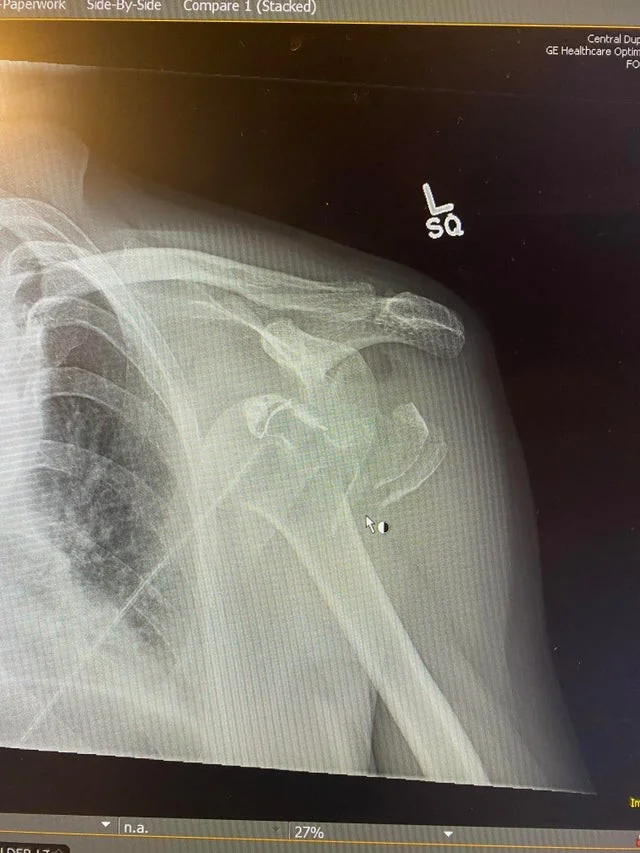

Так выглядит вывихнутое плечо